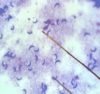

AVIAN COCCIDIA

Schizonts full of

trophozoites or merozoites

Schizonts full of trophozoites or merozoites

AVIAN COCCIDIA

Schizonts full of trophozoites or merozoites